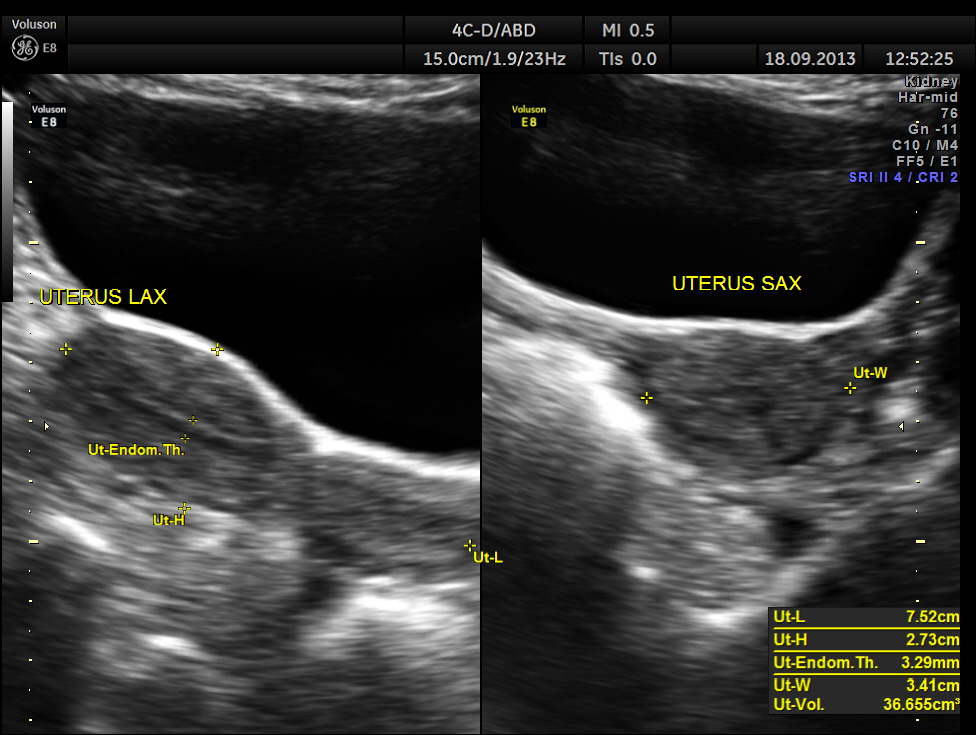

This was a 55 year old lady who had earlier undergone hernia repair surgery few years ago ,following caesarian section done many years ago.

Ultrasound revealed normal liver, gall bladder, pancreas, spleen ,post menopausal shrunk uterus and normal right kidney.